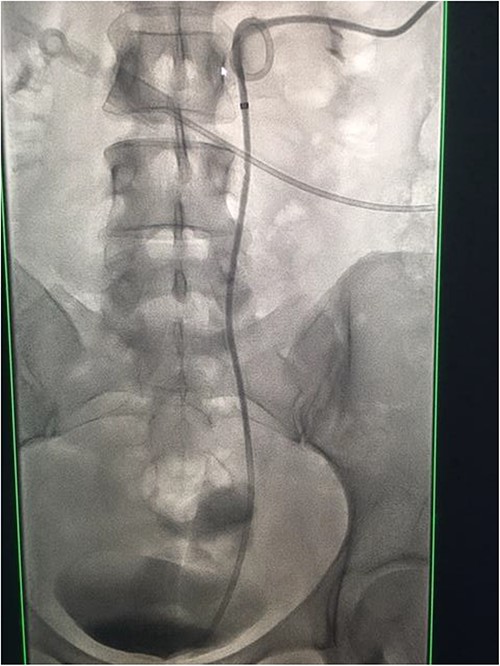

Fluoroscopic images showing the retrograde wire successfully retrieved and brought externally via the nephrostomy site, achieving through-and-through wire access.